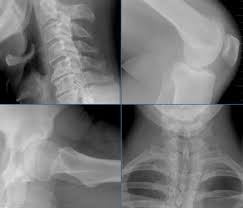

Röntgenbild der gleichen Person fast fehlende Bandscheibe Entzündung ist im Röntgenbild nicht zu erkennen. Es handelt sich um eine Schnittbild im coronaren Strahlengang parallel zur Stirn Der weisse Fleck ist ein Anschnitt der Aorta die dort einen Bogen macht. Bei der Diagnose von Intervertebralhernie und Instabilität der Wirbelsäule in den Bereichen der Übergangswirbel ist es sehr bezeichnend MRI mit Vertikalisierung durchzuführen.